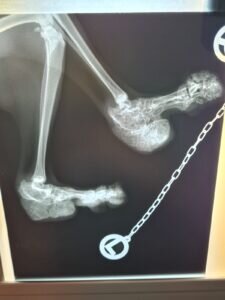

Viele Scottish Fold leiden ihr gesamtes Leben lang unter schmerzhaften degenerativen Gelenkerkrankungen. Die Mutation der Knorpel, die die Knickohren verursacht, verursacht auch die Mutation der Knorpel im Bewegungsapparat. Die Gelenke versteifen, die Knochen verwachsen und jede Bewegung wird mit der Zeit immer beschwerlicher und schmerzhafter.

Wir ließen sie röntgen, wussten aber im Grunde schon, was uns erwarten würde.